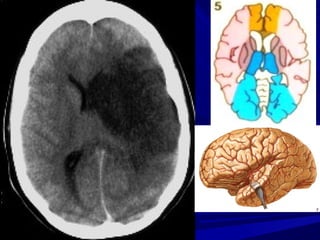

GIAI ÑOAÏN CAÁP SÔÙM (6-24 GIÔØ)

-Giaûm ñaäm ñoä ôû haïch neàn

-Maát ranh giôùi chaát traéng – xaùm

-Daáu daûi baêng thuyø ñaûo (insular ribbon

sign)

-Xoaù raõnh naõo

-Khoâng thaáy baát thöôøng

Mờ Khe Sylvius

Khe Sylvius

Không thấy

Mờ rãnh vỏ não và giảm đậm độ